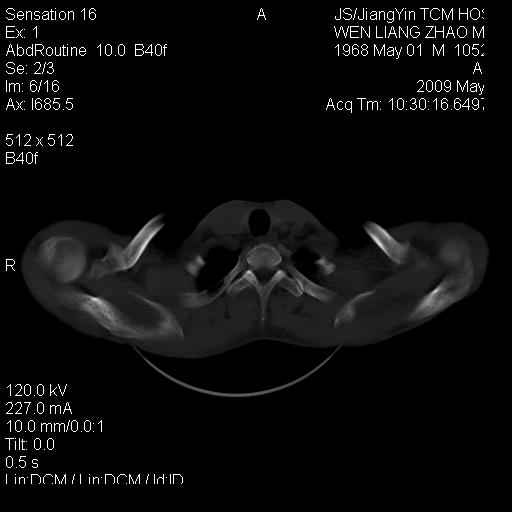

左侧喙突处压痛二年。考虑骨样骨瘤。

病灶外缘膨胀明显,灶缘硬化较少,结合病史较符合骨母细胞瘤,其他亦不排除如软骨及软骨母细胞瘤等(病灶形态,成份较符合,发病部位也符合,只是年龄较大),骨样骨瘤多有较明显的自发性痛,且夜间痛明显,病史为压痛两年,不太符合.

多考虑内生性软骨瘤。年龄及发病部位及病史不支持骨样骨瘤。

首先考虑内生软骨瘤,其次才考虑骨样骨瘤。

良性骨病(低毒感染,成软骨细胞瘤.)